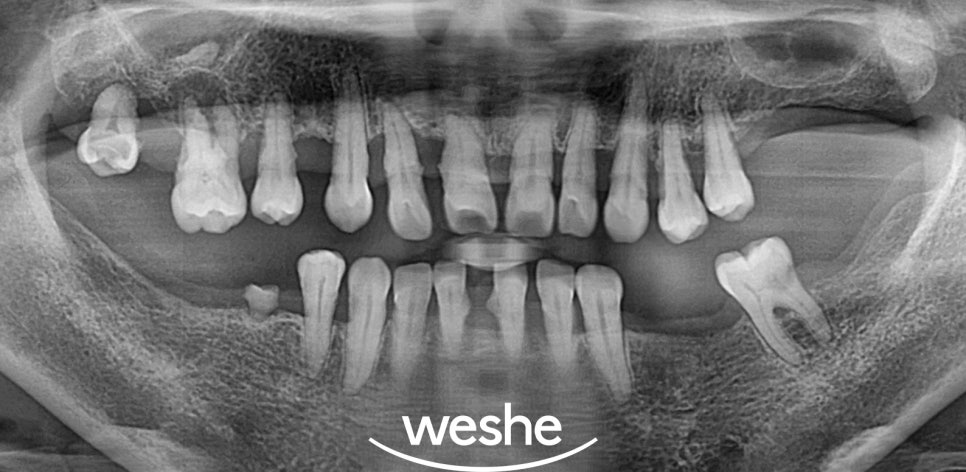

방사선 촬영을 통해

치조골의 흡수 정도와

치아 뿌리 주변의 상태를

정밀하게 분석합니다.

치조골의 흡수가 치아 뿌리

길이의 2/3 이상 진행된 경우,

또는 치아 주변의 치조골이

광범위하게 파괴된 경우에는

해당 부위의 장기적인 예후가

불량한 것으로 평가됩니다.

이러한 상태에서는

지속적인 염증의 원인이 되어

인접한 건강한 치아에까지

악영향을 미칠 수 있습니다.